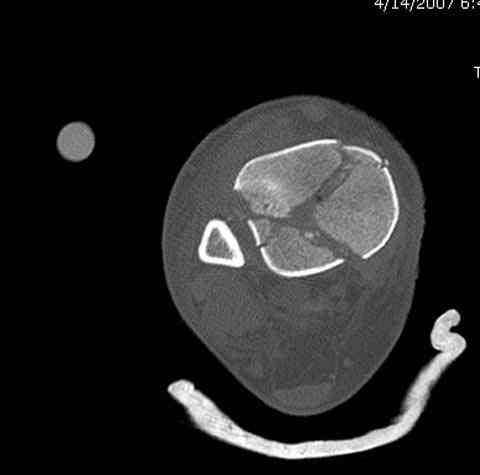

Дополнительные ренгенограммы после дистракции и

обязательная комьютерная томография дают возможности разузнать топографию расположения фрагментов, что немаловажно для планирования хирургического доступа.

Переломы пилона сопровождаются ударом со сминанием в метафизарной части большеберцовой, то есть со значительной потерей костного объема.

При репозиции суставных поверхностей образуются полости в метафизарных отделах, без заполнения их

структуральными элементами невозможно предохраниться от посттравматической деформации. Латеральная колонна удерживается малоберцовой поэтому голень деформируется в варус.

Аутокость является самым надежным материалом, но при желании можно применить синтетический заполнитель Osteoset Pallets - структуральный материал, по аннотации материал через определенное время интегрируется в кость.

Здесь выставлена пара случаев перелома пилона, оба

случая леченные этапным наружным фиксатором.